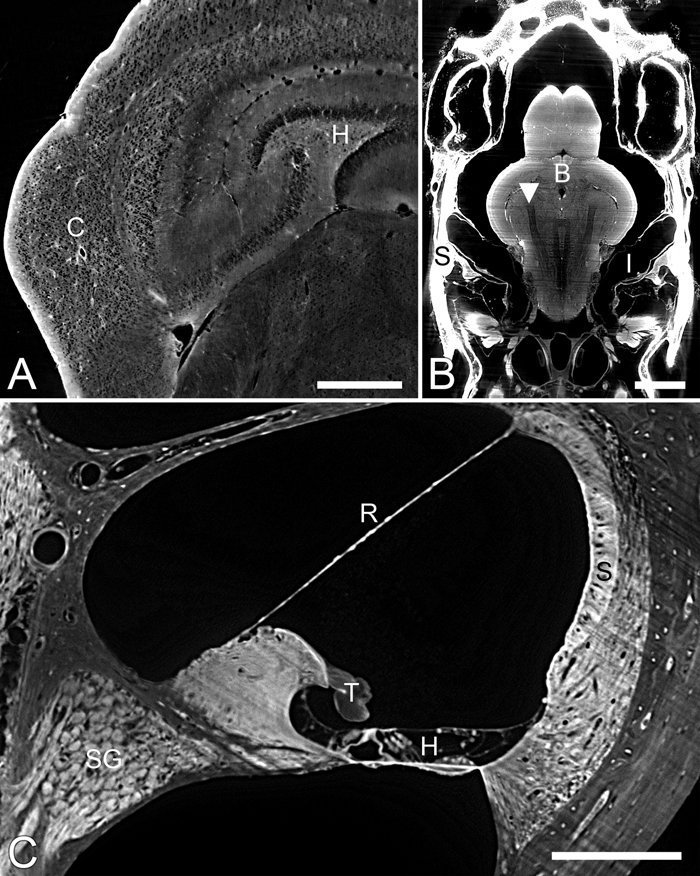

光片的荧光显微镜(LSFM)用作非破坏性切片机和显微镜用途与亚细胞分辨率的光以光学部和视图组织的平面上。这种方法非常适合于透明组织深或整个生物体中进行成像,并且因为组织暴露于光仅一薄层平面,光漂白试样和光毒性最小化相比宽视场荧光,共聚焦,或者多光子显微镜。LSFMs产生适合于组织结构的三维重建以及注册的连续切片。因为缺乏商业LSFM显微镜的,光片显微镜许多版本已经由不同的研究者构成。这篇综述描述了技术的发展,现有装置的评价,提供一个LSFM设备的细节,并且示出了图像和由LSFM中产生的组织的三维重建的示例。